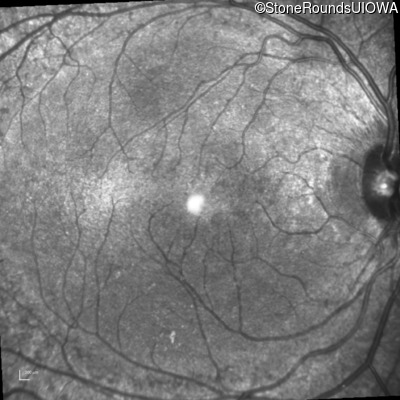

The clinical features supporting the diagnosis of the enhanced S-cone syndrome (ESCS) in this patient include: stable night blindness since at least the second year of life, normally sighted parents, nummular pigment in the mid-periphery of the fundus that stops abruptly at the temporal arcades and disorganization of the retinal layers (seen on OCT) anterior to the temporal arcades.